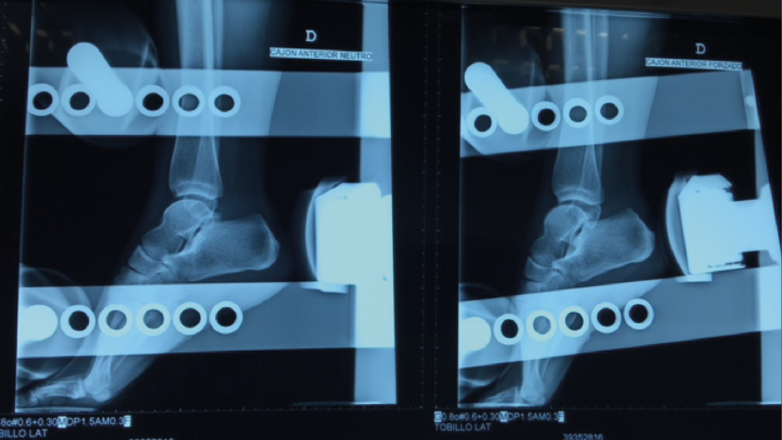

– Cajón anterior: paciente sentado con la rodilla en flexión. Aplicando rotación interna se testa el ligamento peroneo-astragalino anterior (PAA); con rotación externa valoramos la laxitud medial (frecuentemente asociada a dolor anteromedial)(Figura 2).

Figura 2. Maniobra del cajón anterior. Paciente sentado con la pierna colgando a 90°. El cajón anterior con tope óseo pone de manifiesto la insuficiencia del ligamento peroneo-astragalino anterior.

- Cajón anterior: positiva si existe una traslación anterior > 1 cm o una diferencia > 3 mm respecto al tobillo contralateral (Figura 4).

Figura 4. Radiografía del cajón anterior. El cajón anterior es positivo si existe una traslación anterior > 1 cm o una diferencia > 3 mm respecto al tobillo contralateral.